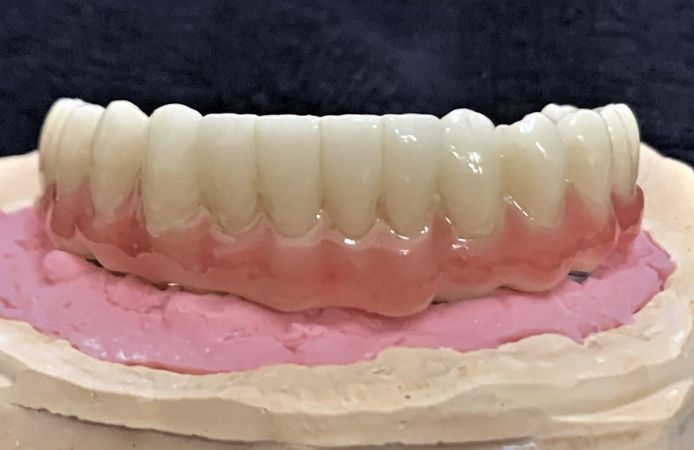

Figure 1.

Figure 2.

Figure 3.

Figure 4.